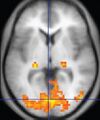

Functional MRI (fMRI) Blood-oxygen-level dependent imaging BOLD Changes in oxygen saturation-dependent magnetism of hemoglobin reflects tissue activity.[35] Localizing highly active brain areas before surgery, also used in research of cognition.[36] 1206 FMRI.jpg